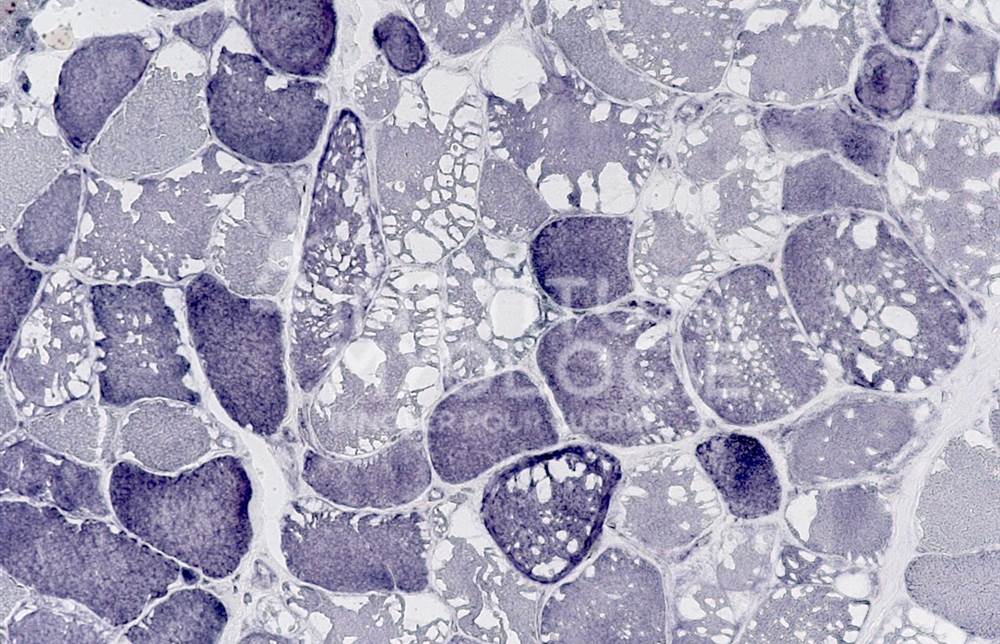

Welcome to the Muscle Atlas, the first database of muscle images designed to facilitate research, diagnosis and knowledge in the field of neuromuscular pathologies. Our vast collection includes more than 6,416 images of muscle biopsies from patients with various diseases and animal models, which may or may not be undergoing treatment. Each image is characterised according to the specific condition and corresponding stage of the disease.